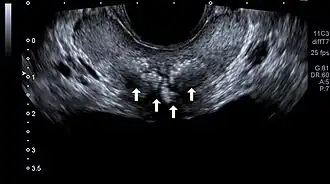

| Transrectal ultrasound of prostatic stones in the peri-urethral zone of the prostate | |

Prostatic calculi (PC), prostatic stones, prostatic calcification or prostatic lithiasis, are hyper-echoic mineral deposits in the prostate that are frequently detected incidentally during transabdominal ultrasonography, transrectal ultrasonography, or computed tomography.[1][2][3]